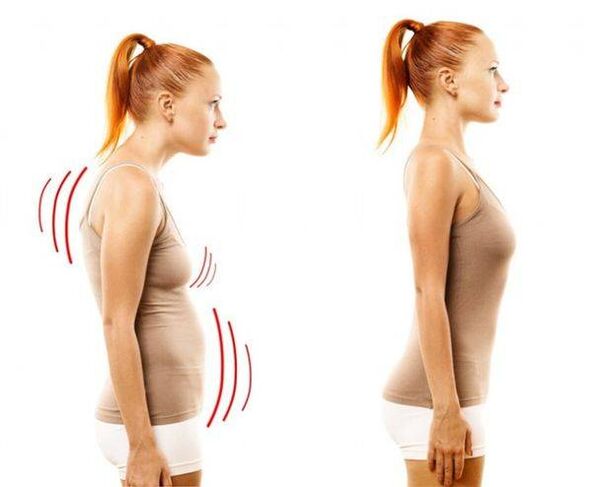

在这种疾病中,椎间盘的核心变薄并干燥,周围的纤维组织开始恶化,软骨组织发生负面变化。事实证明,脊柱无法应对正常的负荷 - 这主要表现为疼痛的出现,这种疼痛最初表现得很模糊,但随着时间的推移变得越来越强烈。然而,由于巨大的压力——久坐的生活方式、久坐的工作、持续的压力、不良姿势和背部受伤——骨软骨病迟早会影响胸部区域。这种疾病被认为非常常见:三分之一的成年人患有这种疾病。

在疾病发展的后期,疼痛症状通常表现为腰痛。疼痛明显、剧烈,干扰正常呼吸,不必要的动作只会加剧情况。腰痛通常是在长时间不活动后开始的,例如在计算机上静态工作几个小时后。

脊柱骨软骨病晚期表现为脊柱侧凸;有时疾病会扩散到颈椎并导致失声。